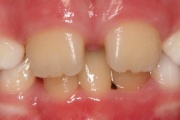

Ravijärgne seis. Jäävhammas on täielikult lõikunud.